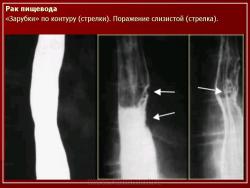

ПС. Пищевод. Набор изображений № 2. Новообразования пищевода. Варикозно расширенные вены пищевода. +

Пищевод.  Набор изображений № 2.